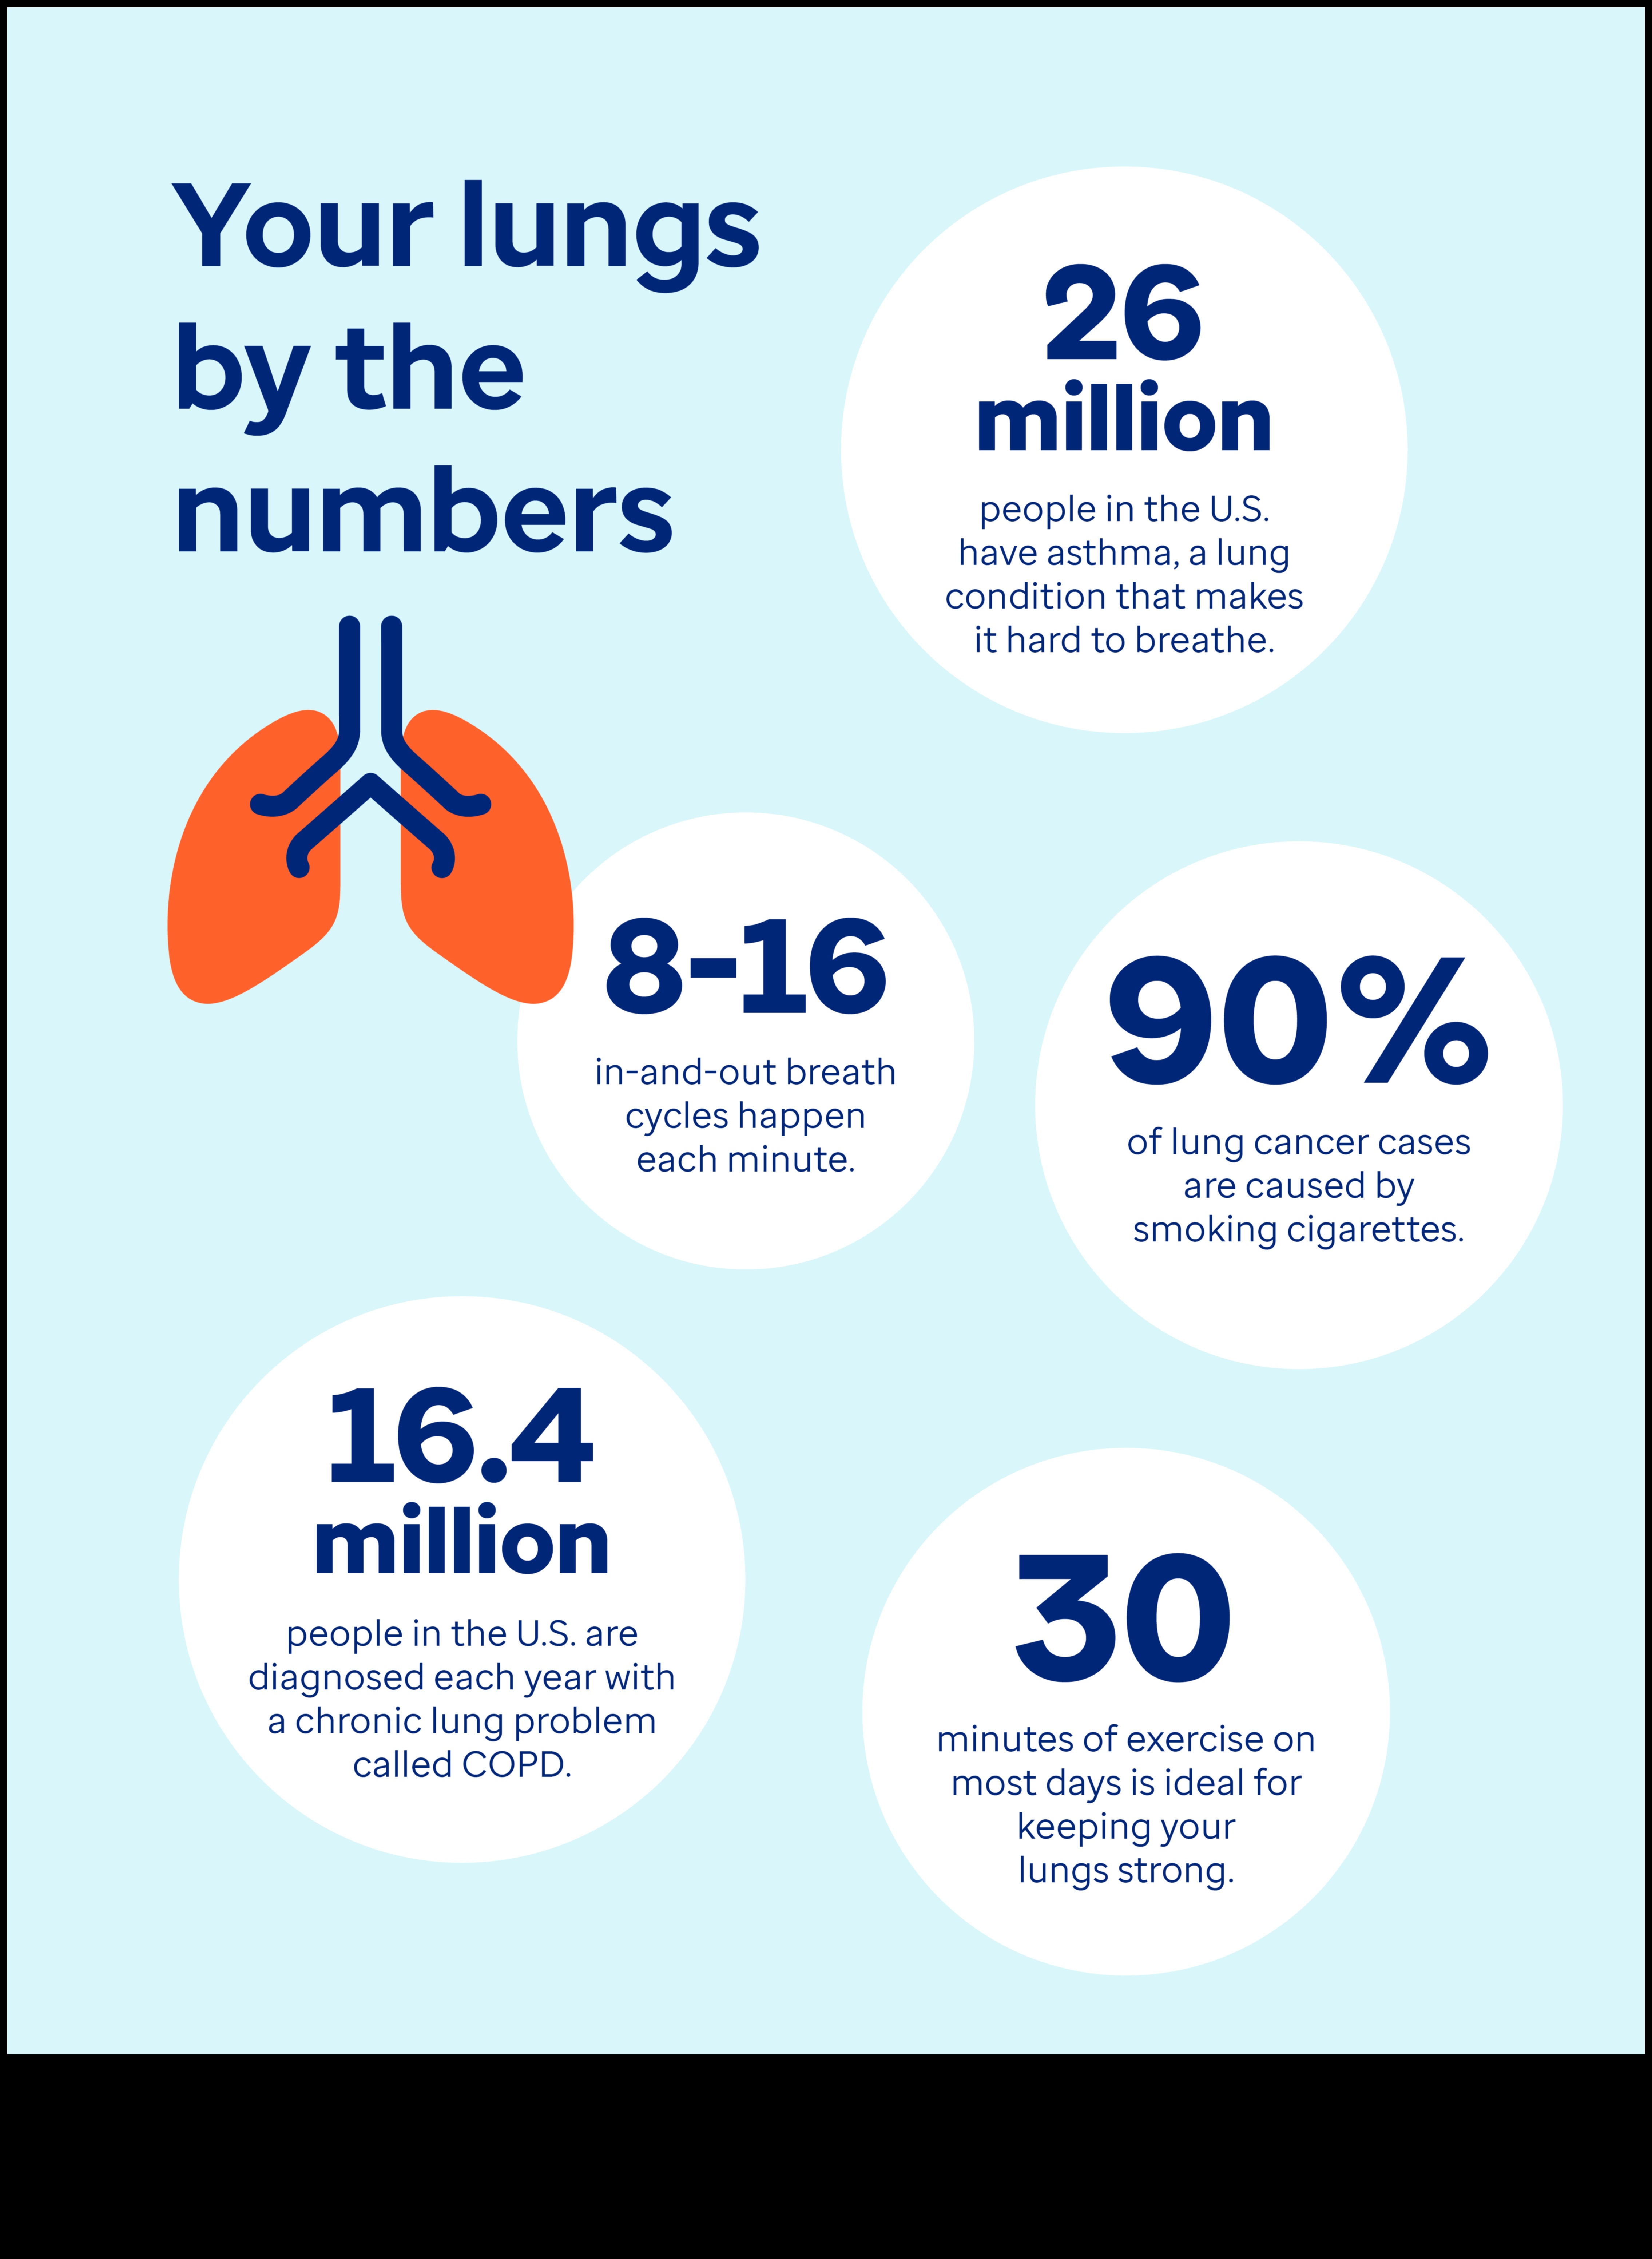

Elpošanas treniņu rutīnas varētu arī atbalstīt spēcināt plaušu darbību un minimizēt astmas simptomus. Viens no svarīgākajiem visizplatītākajiem astmas elpošanas vingrinājumiem ir:

Elpošanas treniņu rutīnas ir seifs un labs veids, padomi, kā spēcināt plaušu darbību un minimizēt astmas simptomus. Ja Jums ir bronhiālā astma, konsultējieties izmantojot savu ārstu attiecībā uz elpošanas vingrinājumu pievienošanu ārstēšanas plānam.

Ir dažādība elpošanas treniņu rutīnas, kas varbūt atbalstīt vecākiem izmantojot astmu kontrolēt simptomus. Tie treniņu rutīnas varētu arī atbalstīt spēcināt plaušu darbību, minimizēt iekaisumu un minimizēt elpas trūkumu.

Astmas slimniekiem pastāvīgi notiek elpas zaudējums, sēkšana un klepus. Tie indikatori parasti ir novājinoši, apgrūtinot standarta darbību veikšanu. No otras puses ir dažādība treniņu rutīnas, kas astmas slimniekiem varētu arī atbalstīt pacelt elpot. Tie treniņu rutīnas varētu arī spēcināt plaušas un spēcināt elpošanas talanti, atvieglojot elpošanu astmas lēkmes gaitā.

Elpošanas vingrinājumiem ir liels skaits ieguvumu, tostarp:

Elpošanas treniņu rutīnas varētu arī atbalstīt spēcināt plaušu kapacitāti, spēcināt elpošanas muskuļus un spēcināt vispārējo elpceļu veselību. Šie varētu arī atbalstīt jums kontrolēt astmas, HOPS un citu elpošanas traucējumu simptomus.